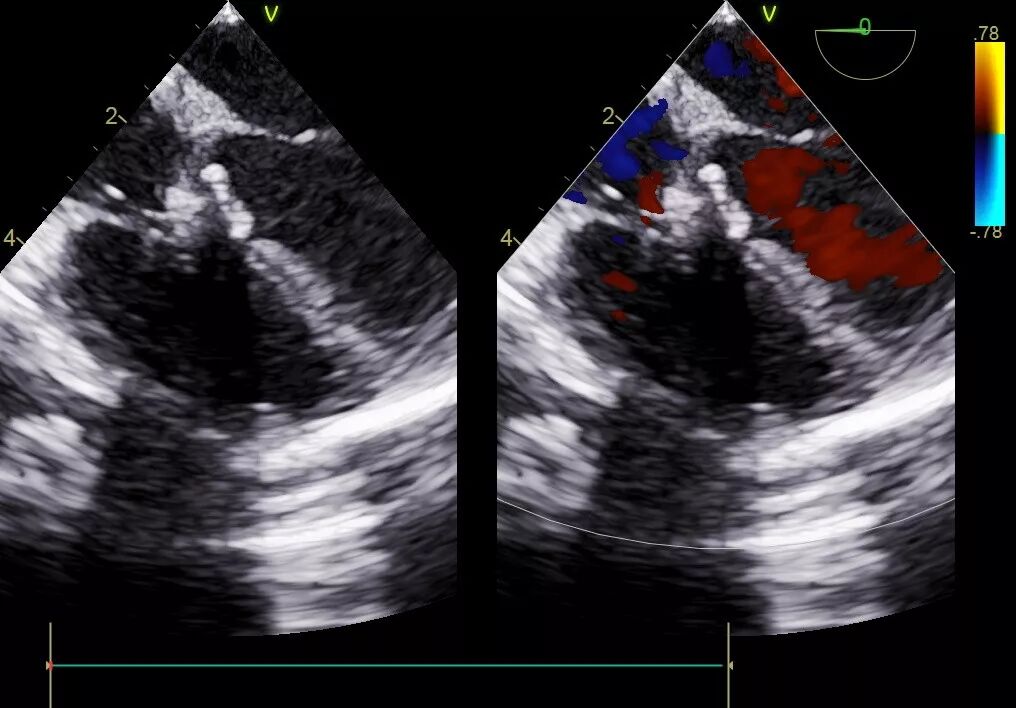

可可术前心脏超声

可可术后心脏超声